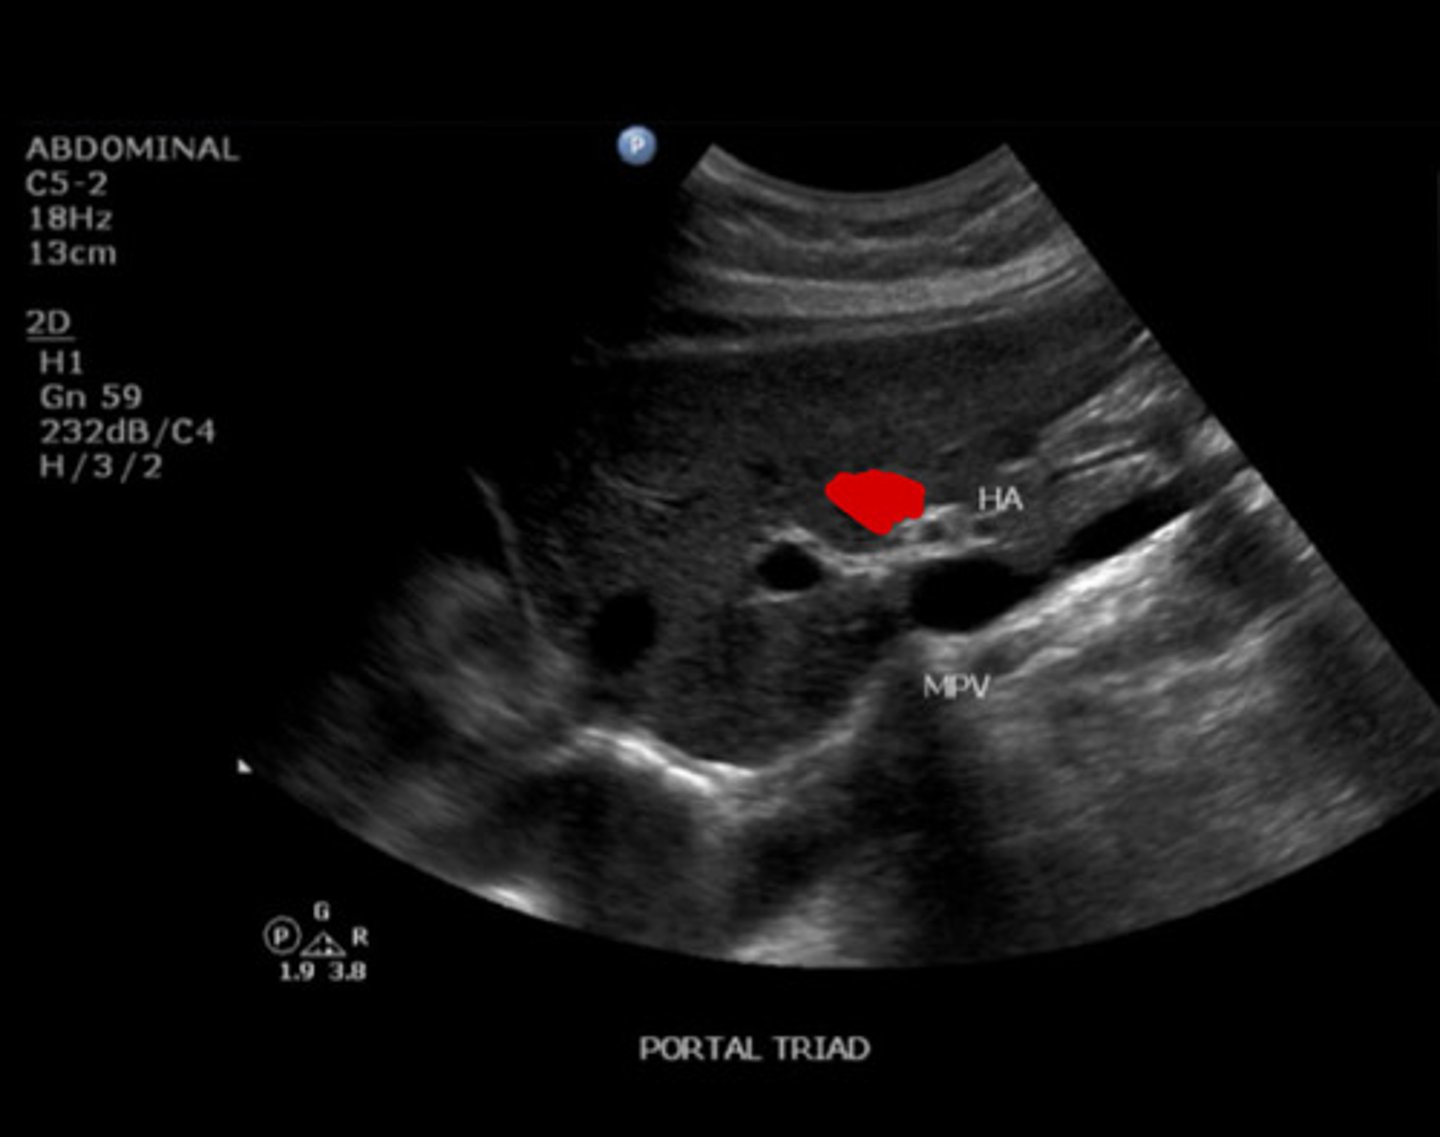

10

New cards

Portal triad

Identify the following;

<p>Identify the following;</p>